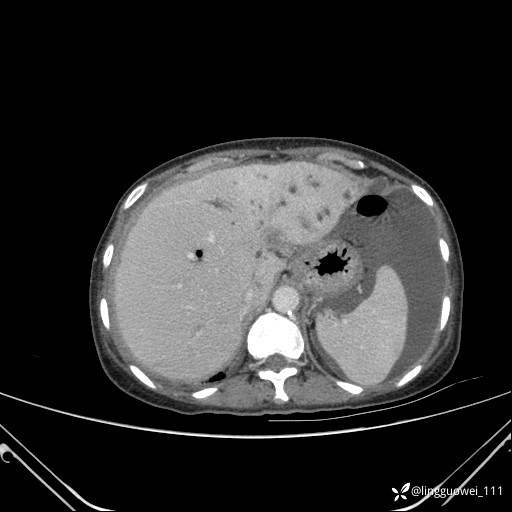

主诉:门诊行胃肠镜检查后,诉腹胀,入院检查,肝有病变吗?腹膜及腹腔的表现有特征性吗?

平扫: